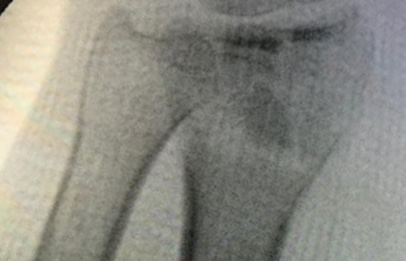

Cirugías de Codo - Cirugías de Muñecas y Manos

Los procedimientos más comunes en cirugía de la mano son aquellos destinados a reparar traumatismos, incluyendo lesiones de tendones, nervios, vasos sanguíneos, y articulaciones; huesos fracturados; y quemaduras, cortes, y otros daños de la piel.